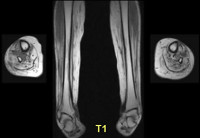

G72.9 Миопатия неуточненная